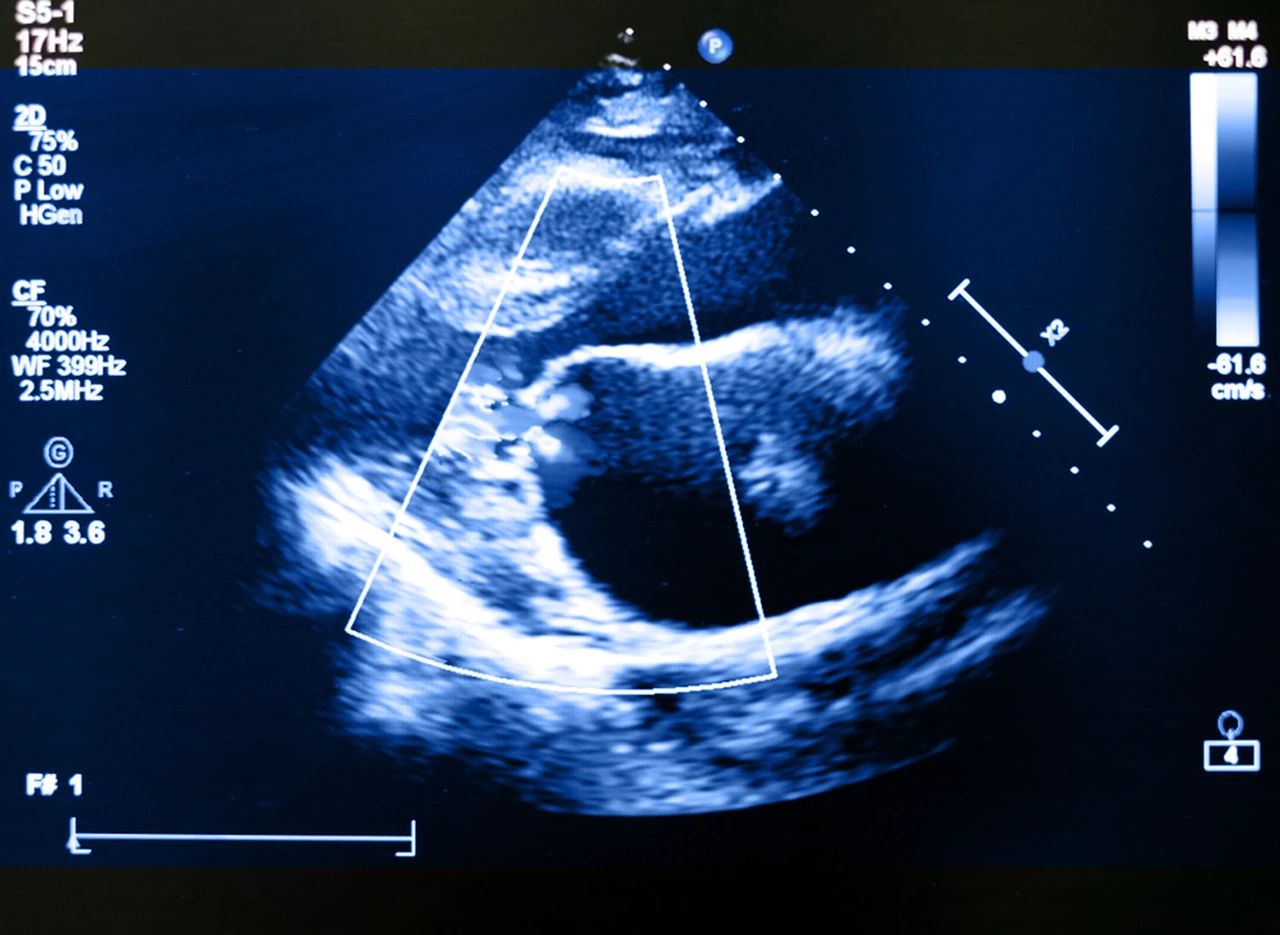

• Ecocardiograma: es el estudio clave. Mediante ultrasonido, el cardiólogo analiza el tamaño del corazón, el grado de fuga de sangre, el grosor de las paredes y la movilidad de la válvula. Aquí también se utiliza la clasificación de Carpentier para insuficiencia mitral, la cual permite identificar el mecanismo del problema (estructural, funcional, por prolapso, etc.) y definir el tratamiento más adecuado.

Ecocardiograma realizado a paciente para llegar al diagnóstico de la insuficiencia mitral.

Un diagnóstico oportuno es fundamental, porque incluso las formas leves pueden progresar sin causar síntomas evidentes.